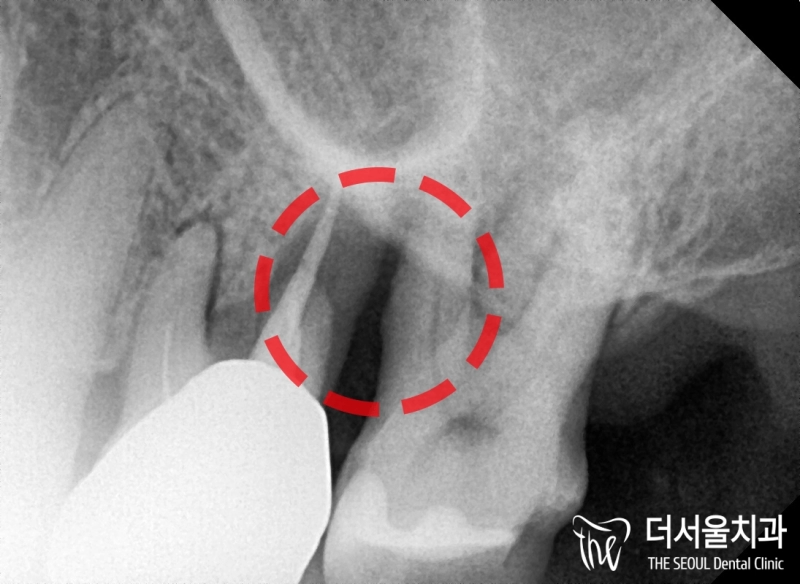

반갑습니다. 잠실 더서울 치과 박현성 원장입니다. 예전에 내원을 하셨던 환자 중에 따님분께 추천을 받아 오게 되었으며, 임플란트 수술을 받았던